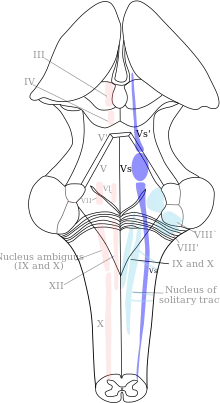

Trigeminal nuclei

All sensory information from the face, both touch-position and pain-temperature, is sent to the trigeminal nucleus. In classical anatomy most sensory information from the face is carried by the fifth nerve, but sensation from parts of the mouth, parts of the ear and parts of the meninges is carried by general somatic afferent fibers in cranial nerves VII (the facial nerve), IX (the glossopharyngeal nerve) and X (the vagus nerve).

All sensory fibers from these nerves terminate in the trigeminal nucleus. On entering the brainstem, sensory fibers from V, VII, IX and X are sorted and sent to the trigeminal nucleus (which contains a sensory map of the face and mouth). The spinal counterparts of the trigeminal nucleus (cells in the dorsal horn and dorsal column nuclei of the spinal cord) contain a sensory map of the rest of the body.

The trigeminal nucleus extends throughout the brainstem, from the midbrain to the medulla, continuing into the cervical cord (where it merges with the dorsal horn cells of the spinal cord). The nucleus is divided into three parts, visible in microscopic sections of the brainstem. From caudal to rostral (ascending from the medulla to the midbrain), they are the spinal trigeminal, the principal sensory and the mesencephalic nuclei. The parts of the trigeminal nucleus receive different types of sensory information; the spinal trigeminal nucleus receives pain-temperature fibers, the principal sensory nucleus receives touch-position fibers and the mesencephalic nucleus receives proprioceptor and mechanoreceptor fibers from the jaws and teeth.

Spinal trigeminal nucleus

The spinal trigeminal nucleus represents pain-temperature sensation from the face. Pain-temperature fibers from peripheral nociceptors are carried in cranial nerves V, VII, IX and X. On entering the brainstem, sensory fibers are grouped and sent to the spinal trigeminal nucleus. This bundle of incoming fibers can be identified in cross-sections of the pons and medulla as the spinal tract of the trigeminal nucleus, which parallels the spinal trigeminal nucleus. The spinal tract of V is analogous to, and continuous with, Lissauer's tract in the spinal cord.

The spinal trigeminal nucleus contains a pain-temperature sensory map of the face and mouth. From the spinal trigeminal nucleus, secondary fibers cross the midline and ascend in the trigeminothalamic (quintothalamic) tract to the contralateral thalamus. Pain-temperature fibers are sent to multiple thalamic nuclei. The central processing of pain-temperature information differs from the processing of touch-position information.

Principal nucleus

The principal nucleus represents touch-pressure sensation from the face. It is located in the pons, near the entrance for the fifth nerve. Fibers carrying touch-position information from the face and mouth via cranial nerves V, VII, IX, and X are sent to this nucleus when they enter the brainstem.

The principal nucleus contains a touch-position sensory map of the face and mouth, just as the spinal trigeminal nucleus contains a complete pain-temperature map. This nucleus is analogous to the dorsal column nuclei (the gracile and cuneate nuclei) of the spinal cord, which contain a touch-position map of the rest of the body.

From the principal nucleus, secondary fibers cross the midline and ascend in the ventral trigeminothalamic tract to the contralateral thalamus. The ventral trigeminothalamic tract runs parallel to the medial lemniscus, which carries touch-position information from the rest of the body to the thalamus.

Some sensory information from the teeth and jaws is sent from the principal nucleus to the ipsilateral thalamus via the small dorsal trigeminal tract. Touch-position information from the teeth and jaws of one side of the face is represented bilaterally in the thalamus and cortex.

Mesencephalic nucleus

The mesencephalic nucleus is not a true nucleus; it is a sensory ganglion (like the trigeminal ganglion) embedded in the brainstem and the sole exception to the rule that sensory information passes through peripheral sensory ganglia before entering the central nervous system. It has been found in all vertebrates except lampreys and hagfishes. They are the only vertebrates without jaws and have specific cells in their brainstems. These "internal ganglion" cells were discovered in the late 19th century by medical student Sigmund Freud.

Two types of sensory fibers have cell bodies in the mesencephalic nucleus: proprioceptor fibers from the jaw and mechanoreceptor fibers from the teeth. Some of these incoming fibers go to the motor nucleus of the trigeminal nerve (V), bypassing the pathways for conscious perception. The jaw jerk reflex is an example; tapping the jaw elicits a reflex closure of the jaw in the same way that tapping the knee elicits a reflex kick of the lower leg. Other incoming fibers from the teeth and jaws go to the main nucleus of V. This information is projected bilaterally to the thalamus and available for conscious perception.